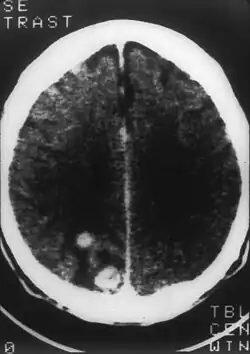

- toxoplasmoza duce, în cursul SIDA, la reactivarea unei infecții vechi, care trece neobservată. Ea antrenează tulburări neurologice majore în caz de localizare cerebrală.